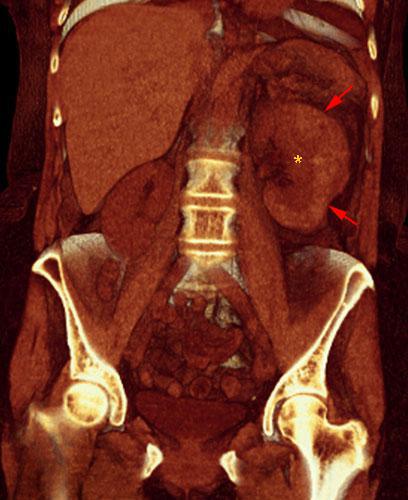

Hematoma subcapsular y perirrenal